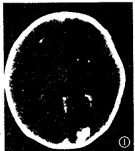

本组病例初次头颅CT扫描时间:最早在生后1天,最迟23天,平均3.8天,诊断为不同程度的 HIE。结合文献[1],根据CT所见的脑水肿范围、程度,将本组HIE分为轻、中、重 3度:轻度者43例,脑实质内斑片状低密度灶,常见于额叶、枕顶叶,合并蛛网膜下腔出血( SAH) 38例,脑室内出血(IVH) 7例,硬膜下血肿(SDH) 1例,脑实质内出血(ICH) 2例,脑室 、脑池大小、形态正常;中度者14例,脑实质内广泛斑片状低密度灶,累及额颞枕顶叶,灰 白质界限模糊,脑室、脑池变窄,合并SAH 7例,IVH 3例,室管膜下出血(SEH)2例;重度 者5例,脑实质内弥漫性低密度灶,灰白质界限消失,脑室、脑池、脑沟变窄或消失(图1), 合并SAH 5例,IVH 1例,SDH 1例,ICH 1例。

图1 重 度HIE:大脑密度普遍性减低,灰白质界限消失,基底节区密度相对较高,右额叶、左枕叶 出血灶,脑室、脑池及脑沟变窄。